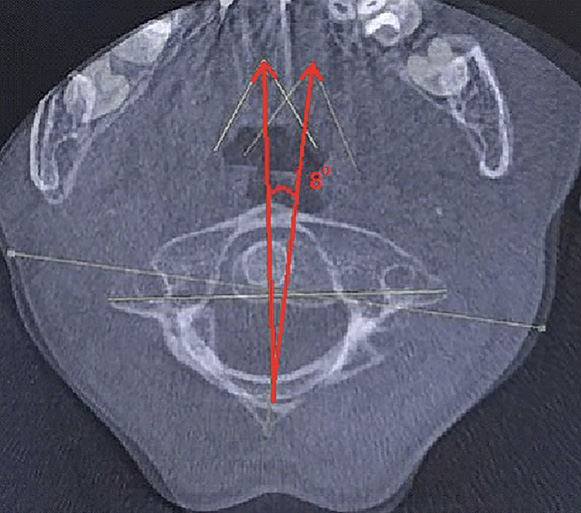

Пациентка Е. 9 лет обратилась на прием с жалобами на ограничение поворотов головой. Со слов матери, в мае 2018 г. ребенку проводилось оперативное лечение по поводу травмы шейного отдела позвоночника. Медицинские заключения не были предоставлены. При осмотре ребенок с синдромом Дауна. Голова по средней линии, пальпация области шейного отдела позвоночника безболезненна, объем пассивных и активных наклонов головы соответствовал нормативным значениям. При этом амплитуда пассивных и активных ротационных движений в шейном отделе позвоночника составила 15° и 20º в каждую сторону соответственно. При последующем ортопедическом осмотре было выявлено нарушение осанки по типу «сутулая спина» по Штаффелю. По данным анализа представленного диска с результатами ранее проведенной мультиспиральной компьютерной томографии шейного отдела позвоночника (дата исследования – май 2018 г.) был выявлен перелом зубовидного отростка С2 позвонка типа 1 по классификации L. D. Anderson и R.T. D'Alonzo, со смещением верхушки зубовидного отростка кпереди [9]. Плоскость перелома зубовидного отростка аксиса косая, края отломков неровные, нечеткие, диастаз между отломками неравномерный (рис. 5).

Рис. 5. Компьютерная томография шейного отдела позвоночника, сагиттальный срез (А), фронтальный срез на уровне зубовидного отростка С2 позвонка (Б). Стрелкой обозначено место перелома зубовидного отростка С2 позвонка